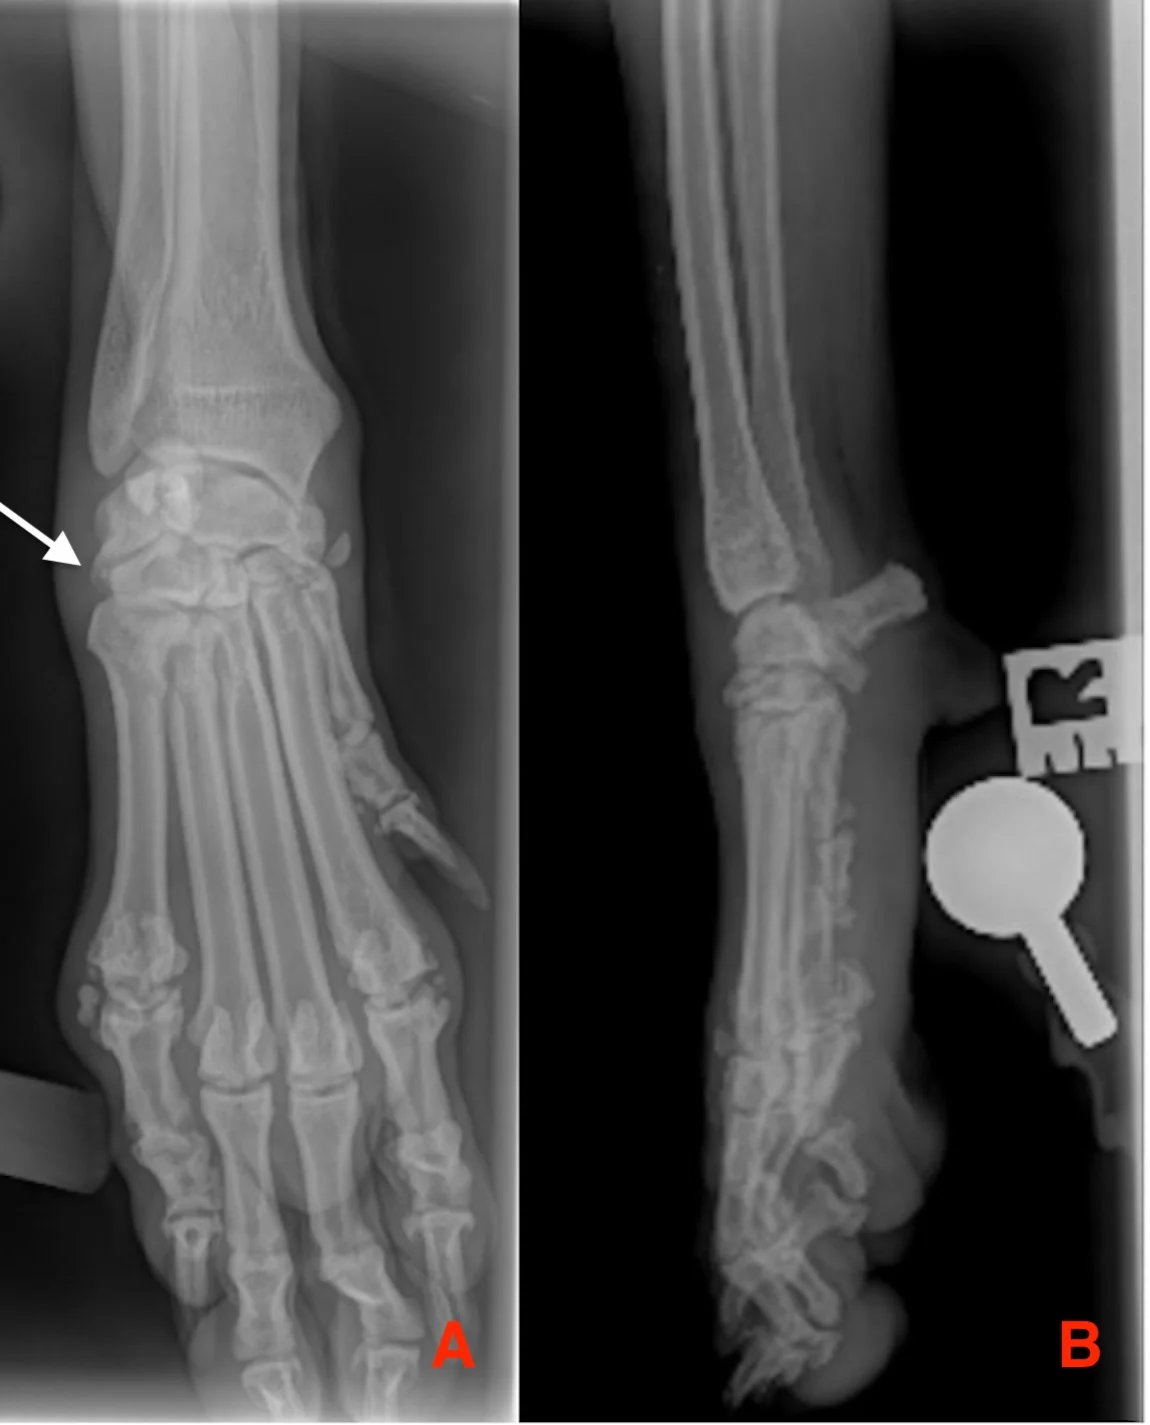

CT images were also taken of the patient in Figure 4. Multiplanar reconstruction was created. A transverse view of the carpus at the level of the distal carpal row, with multiple fractures (arrows) of the second, third, and fourth carpal bones (A); dorsal reconstruction showing a fracture of the second carpal bone (B); and sagittal reconstruction (C) can be seen.